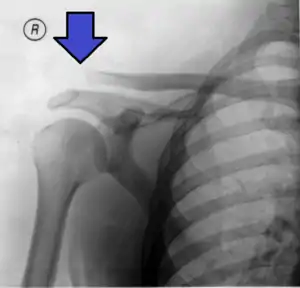

| An Xray showing a separated shoulder. Notice the separation between the end of the collarbone and the scapula. | |

X-ray indicates a separated shoulder when the acromioclavicular joint space is widened (it is normally 5 to 8 mm).[8]